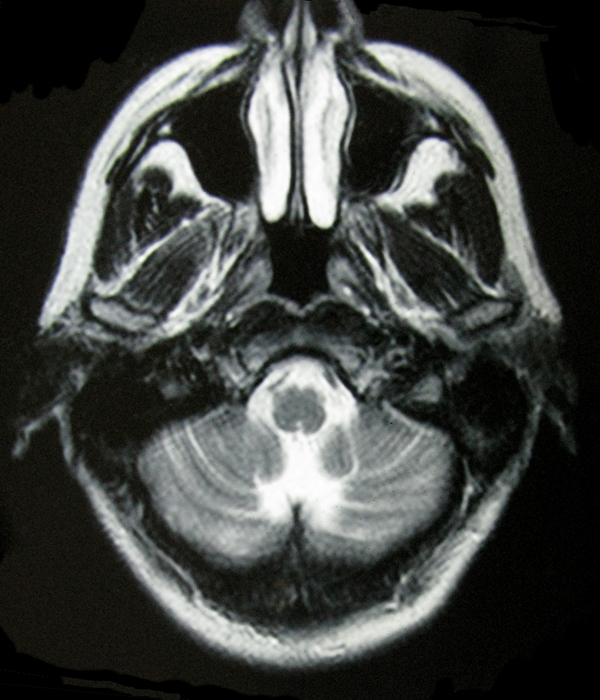

- My Brain in 2009